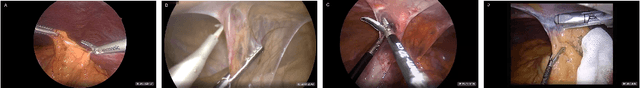

Figure 1 for "Train one, Classify one, Teach one" -- Cross-surgery transfer learning for surgical step recognition